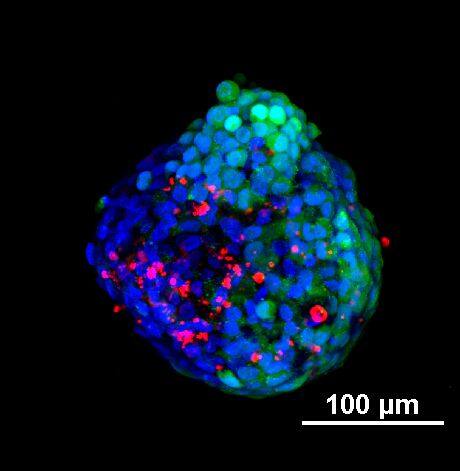

为了生成 3D 球体,将 NCI-H460 细胞(源自非小细胞肺癌)以两种不同的密度接种在超低吸附培养板中:3×103 个细胞/孔或 700 个细胞/孔。在直径分别达到约 400-500 或 150-200 um 后,用细胞毒素剂处理球体 6 天。通过使用钙黄绿素 AM 和碘化丙啶 (PI) 的活/死染色来观察和评估药物的效果。钙黄绿素 AM 是一种细胞渗透性染料,用于测定细胞活性。非荧光钙黄绿素 AM 在活细胞中被细胞内酯酶水解后转化为(绿色)荧光钙黄绿素。PI 是一种红色荧光核染色剂,通常用于检测死亡细胞,因为它不能进入完整的活细胞。最后,使用 Hoechst 染料将细胞核染成蓝色。

我们采用 CrestOptics X-Light V3 转盘共聚焦结合 Prime BSI 相机(Photometrics,像素尺寸 6.5 um)进行采集。我们比较了使用 20 倍空气物镜(CFI Plan Apo Lambda,尼康,0.7 NA 和 1mm WD)和 25 倍硅油物镜(CFI Plan Apo Lambda S,尼康,1.05 NA 和 0.55 mm WD)进行的采集。在图 A 中,我们展示了从总共 150 um 的 Z 堆栈中获得的最大强度投影 (MIP) 图像;特别是,使用 20 倍空气物镜和 25 倍硅油物镜获得了相同的球体。图 B 显示了使用两种物镜获得的 3D 球体同一区域的放大。

使用 20 倍空气物镜和使用 25 倍硅油物镜获得的图像之间的比较(图 A、B 和 C)突出了基于生物应用的透镜选择的重要性。从 20 倍到 25 倍的转换导致分辨率提高(基于 25 倍的 NA 大于 20 倍 NA),这当然会影响图像质量,并且还会导致光折射减少。事实上,浸油通过用更高折射率的介质代替透镜和盖玻片之间的空气间隙,大大提高了显微镜的分辨率,从而减少了光的折射。

在 3D 成像中,样品的折射率与其浸没介质的折射率相匹配对于深层组织观察至关重要。硅酮浸油非常适合透过厚厚的生物样本进行成像;它与细胞和封固剂的折射率非常吻合,与使用普通 20 倍空气物镜获得的图像相比,减少了球面像差,产生了更亮、分辨率更高的图像。

图 A:使用 20 倍空气物镜(顶部)和 25 倍硅油物镜(底部)获得的肿瘤球体 Z 堆栈的最大密度投影 (MIP)。活细胞用钙黄绿素(绿色)标记,死细胞用 PI(红色)标记。细胞核用 Hoechst(蓝色)染色。比例尺:100 um。这些图像是使用 CrestOptics X-Light V3 转盘获取的。